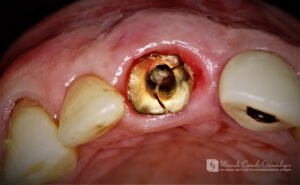

RESTAURAÇÃO SIMULTÂNEA: Óssea, gengival, após fratura da raiz dentária Última modificação do post:22 de outubro de 2025 Tempo de leitura:1 minuto de leitura Comentários do post:0 comentário * Clique nas imagens para ampliar Finalização com coroas de cerâmica.Acompanhamento de um ano. Tags: #implantes, #marcelocameloodontologia, #oralhealth, #periodontia, #periodontite, #periodontitis, #procedimentosodotonologicos, #restauraçãosimultânea, #tratamentosdentarios Leia mais artigos Post anteriorA REVOLUÇÃO EM TRATAMENTOS DE PERIODONTITE E PERIOIMPLANTES Próximo postFINALMENTE, PODEMOS SABER O QUE CAUSA A DOENÇA DE ALZHEIMER E COMO PARÁ-LA Você também pode gostar PROSPECTIVE 1-Year Study of Immediately Loaded Implants: 8-Patient Case Series Report 22 de setembro de 2025 Regeneração de Papilas-I 15 de outubro de 2025 CONTATO ENTRE OS DENTES DAS ARCADAS SUPERIOR E INFERIOR 22 de setembro de 2025 Deixe um comentário Cancelar respostaComentárioDigite seu nome ou nome de usuário para comentar Digite seu endereço de e-mail para comentar Digite o URL do seu site (opcional) Salvar meus dados neste navegador para a próxima vez que eu comentar.